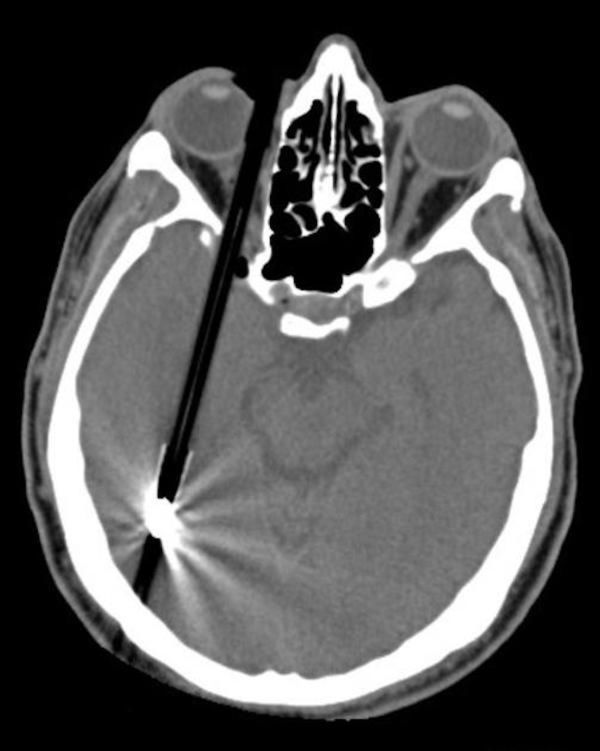

13 / 15Ołówek

Przykra sprawa.